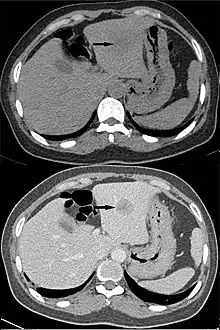

顯影消退

顯影消退(washout)是指顯影劑在動脈相階段被組織吸收後,於靜脈相階段等後續階段逐漸消退的現象。例如,肝細胞癌的顯影電腦斷層掃描中,透過分析腫瘤部位和肝實質部位顯影的時間差,可判斷腫瘤的大小和位置。[4]